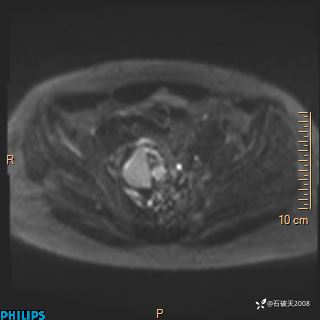

现病史:7个月前患者因骶尾部占位就诊于北京大学人民医院,MRI示:骶骨右侧及右骶前占位,考虑骨巨细胞瘤可能,动脉瘤样骨囊肿可能,神经源性肿瘤待排。行手术治疗,术后病理回示:XXXXX。术后给予对症治疗,具体不详,恢复良好。近几个月反复出现发热,伴骶尾部不适,多次住院给予对症治疗,2天前患者无明显诱因再次发热伴骶尾部不适,无大小便失禁,为求进一步治疗,遂门诊来我院,在门诊初步检查后,以“骶尾部肿物”为诊断收入我科。入院来患者神志清,精神一般,饮食睡眠可,大小便无明显异常,体重无下降。

2023年3月份MRI影像

增强轴位